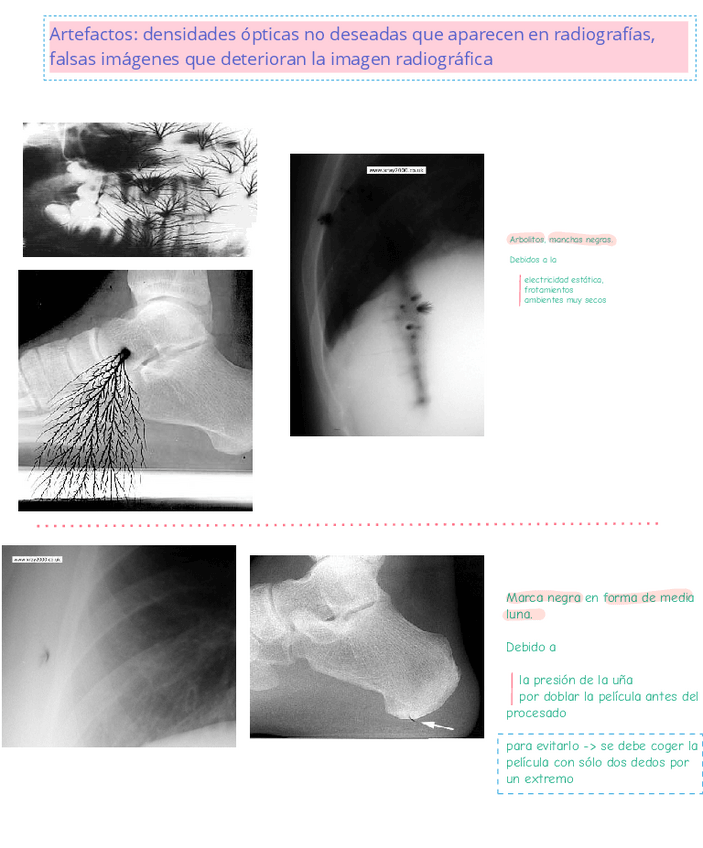

He publicado nuevos apuntes de Fundamentos Físicos y Equipos: artefactos fundamentos .pdf